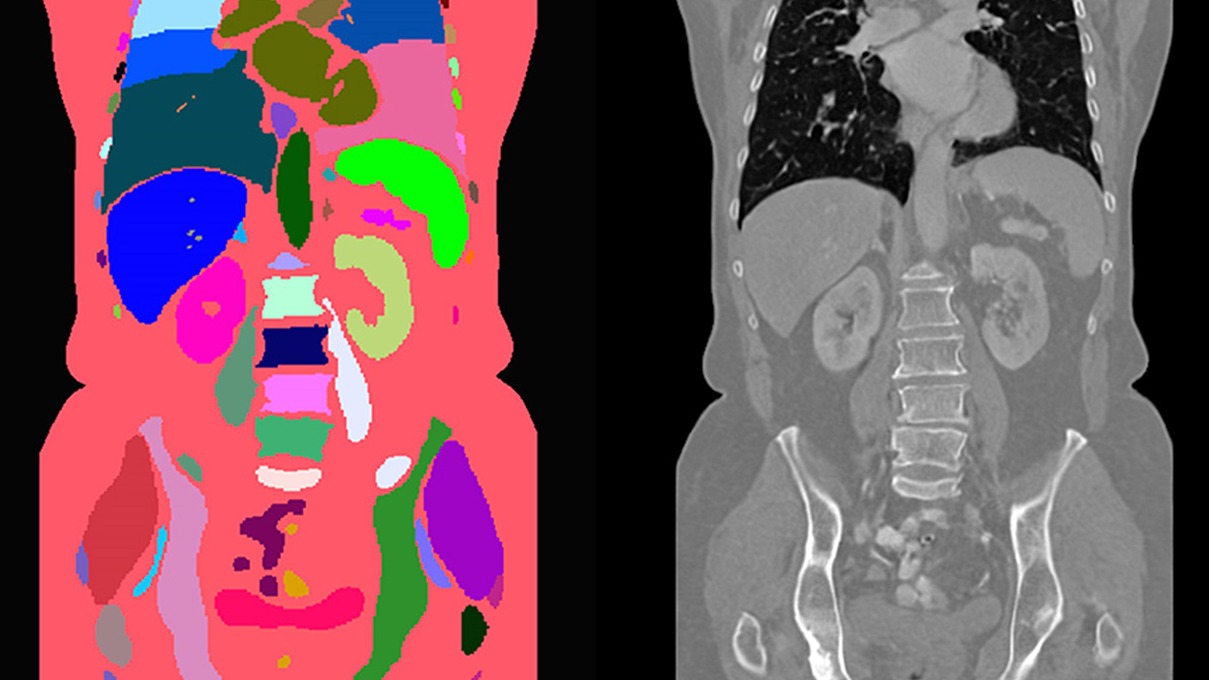

MAISI(Medical AI for Synthetic Imaging)是一种创新的基于扩散模型的方法,用于生成合成的3D计算机断层扫描(CT)图像,以应对上述挑战。MAISI利用基础体积压缩网络和潜在扩散模型,生成高分辨率CT图像,体积尺寸灵活,体素间距可调。通过引入ControlNet,MAISI能够处理包括127个解剖结构的器官分割图作为额外条件,生成带有准确标注的合成图像,适用于各种下游任务。

ControlNet被集成到MAISI框架中,提供了一种机制,可以在更广泛的动态控制下生成输出。它允许通过注入额外条件(如分割掩模、肿瘤掩模等)来控制生成过程,从而在不同任务或临床目标之间转换时,最小化对基础模型的广泛重新训练需求,节省时间和计算资源。

图 4 显示了三例异常病例的定性评估,可以看出 MAISI 在正常器官和异常肿瘤区域都能产生良好的 CT 生成质量,如每个子图的方框所示。我们的结果表明 MAISI 能以高保真度有效地描绘异常组织边界,证明了其在医学成像中基于分割掩模条件捕捉复杂细节方面的稳健性,MAISI 有可能有效地增强生成的 CT 图像的多样性和真实性用于数据增强目的。